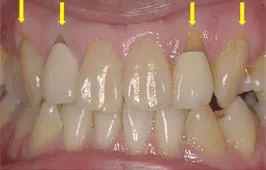

初診時

歯周組織の急性症状により来院されました。細菌検査により悪性の歯周病原因菌(P.gingivalis)が高い割合で検出されたため、抗菌療法を併用し初期治療を行いました。

初期治療終了時